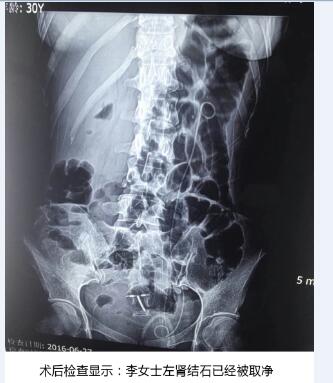

在天津百信医院结石病诊疗首席专家丁德刚主任的带领下,经过专家组周密讨论和精心会诊,一致认为该手术对医生技术和设备要求极高。如果对肾脏结构把握不好,容易造成术中出血量多,肾脏损伤大。最终决定为李女士实施PCN+EMS术式(经皮肾镜联合超声碎石取石术)。从天津百信医院结石病诊疗首席专家丁德刚主任口中得知,该术最大的优势——利用超声碎石清石系统将结石击碎吸出,再利用等渗盐水冲洗,冲出微小结石碎块,术中患者出血很少,手术非常成功。术后检查结果显示,取石率达到100%。

经过1个半小时手术,一次性将李女士体内“心形”结石清除干净,手术非常顺利。